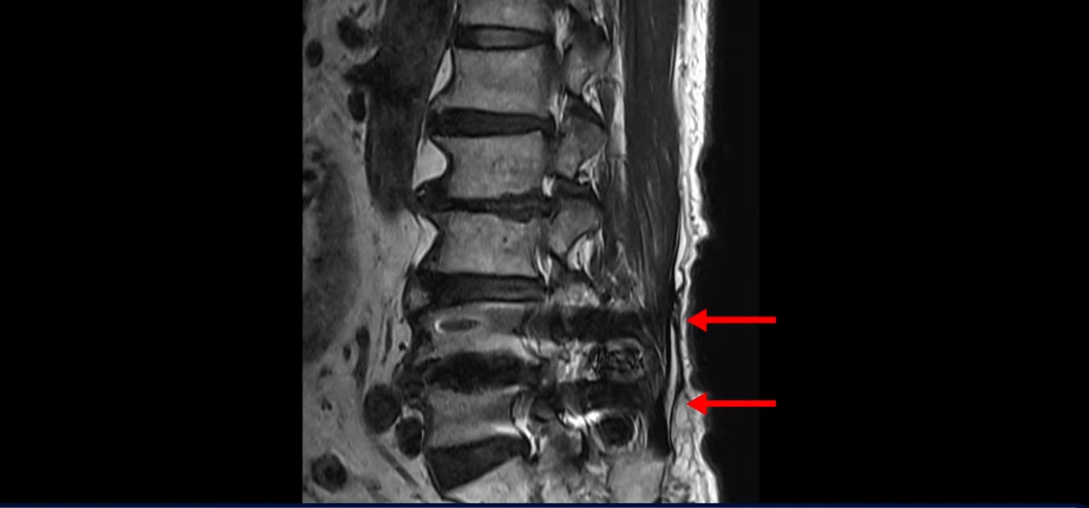

이분 허리 MRI를 보면서 간단히 설명드린 후 유합술 이후 인접마디에 문제가 생긴 환자분들이 왜 추가적인 수술을 서두르기보다는 허리기능을 살려주는 근육신경재활치료를 받는 게 좋은지, 또 치료는 어떻게 하는 게 좋은지 자세히 설명드리겠습니다. 이분 MRI를 보면 4번 5번에 나사가 박혀있습니다.

이렇게 나사가 박혀있으면 그 위나 아래에 문제가 많이 생기고 그걸 인접분절질환이라고 부릅니다. 이분도 유합술을 받은 그 윗마디인 2번 3번에서 디스크가 터져 밀려나와서 수술을 받았는데

이게 수술 후 사진인데도 여전히 척추관은 좁습니다.

나사 박은 마디 위쪽에 수술을 받았지만 수술 후에도 전혀 통증이 좋아지지 않고 다리에 힘도 빠져서 워커를 잡고 겨우 걷는 상태였습니다. 이렇게 유합술 이후 그 위나 아래에 문제가 생기는 인접분절질환은 모든 척추질환 중 가장 치료가 어려운 질환 중 하나로 꼽힙니다.